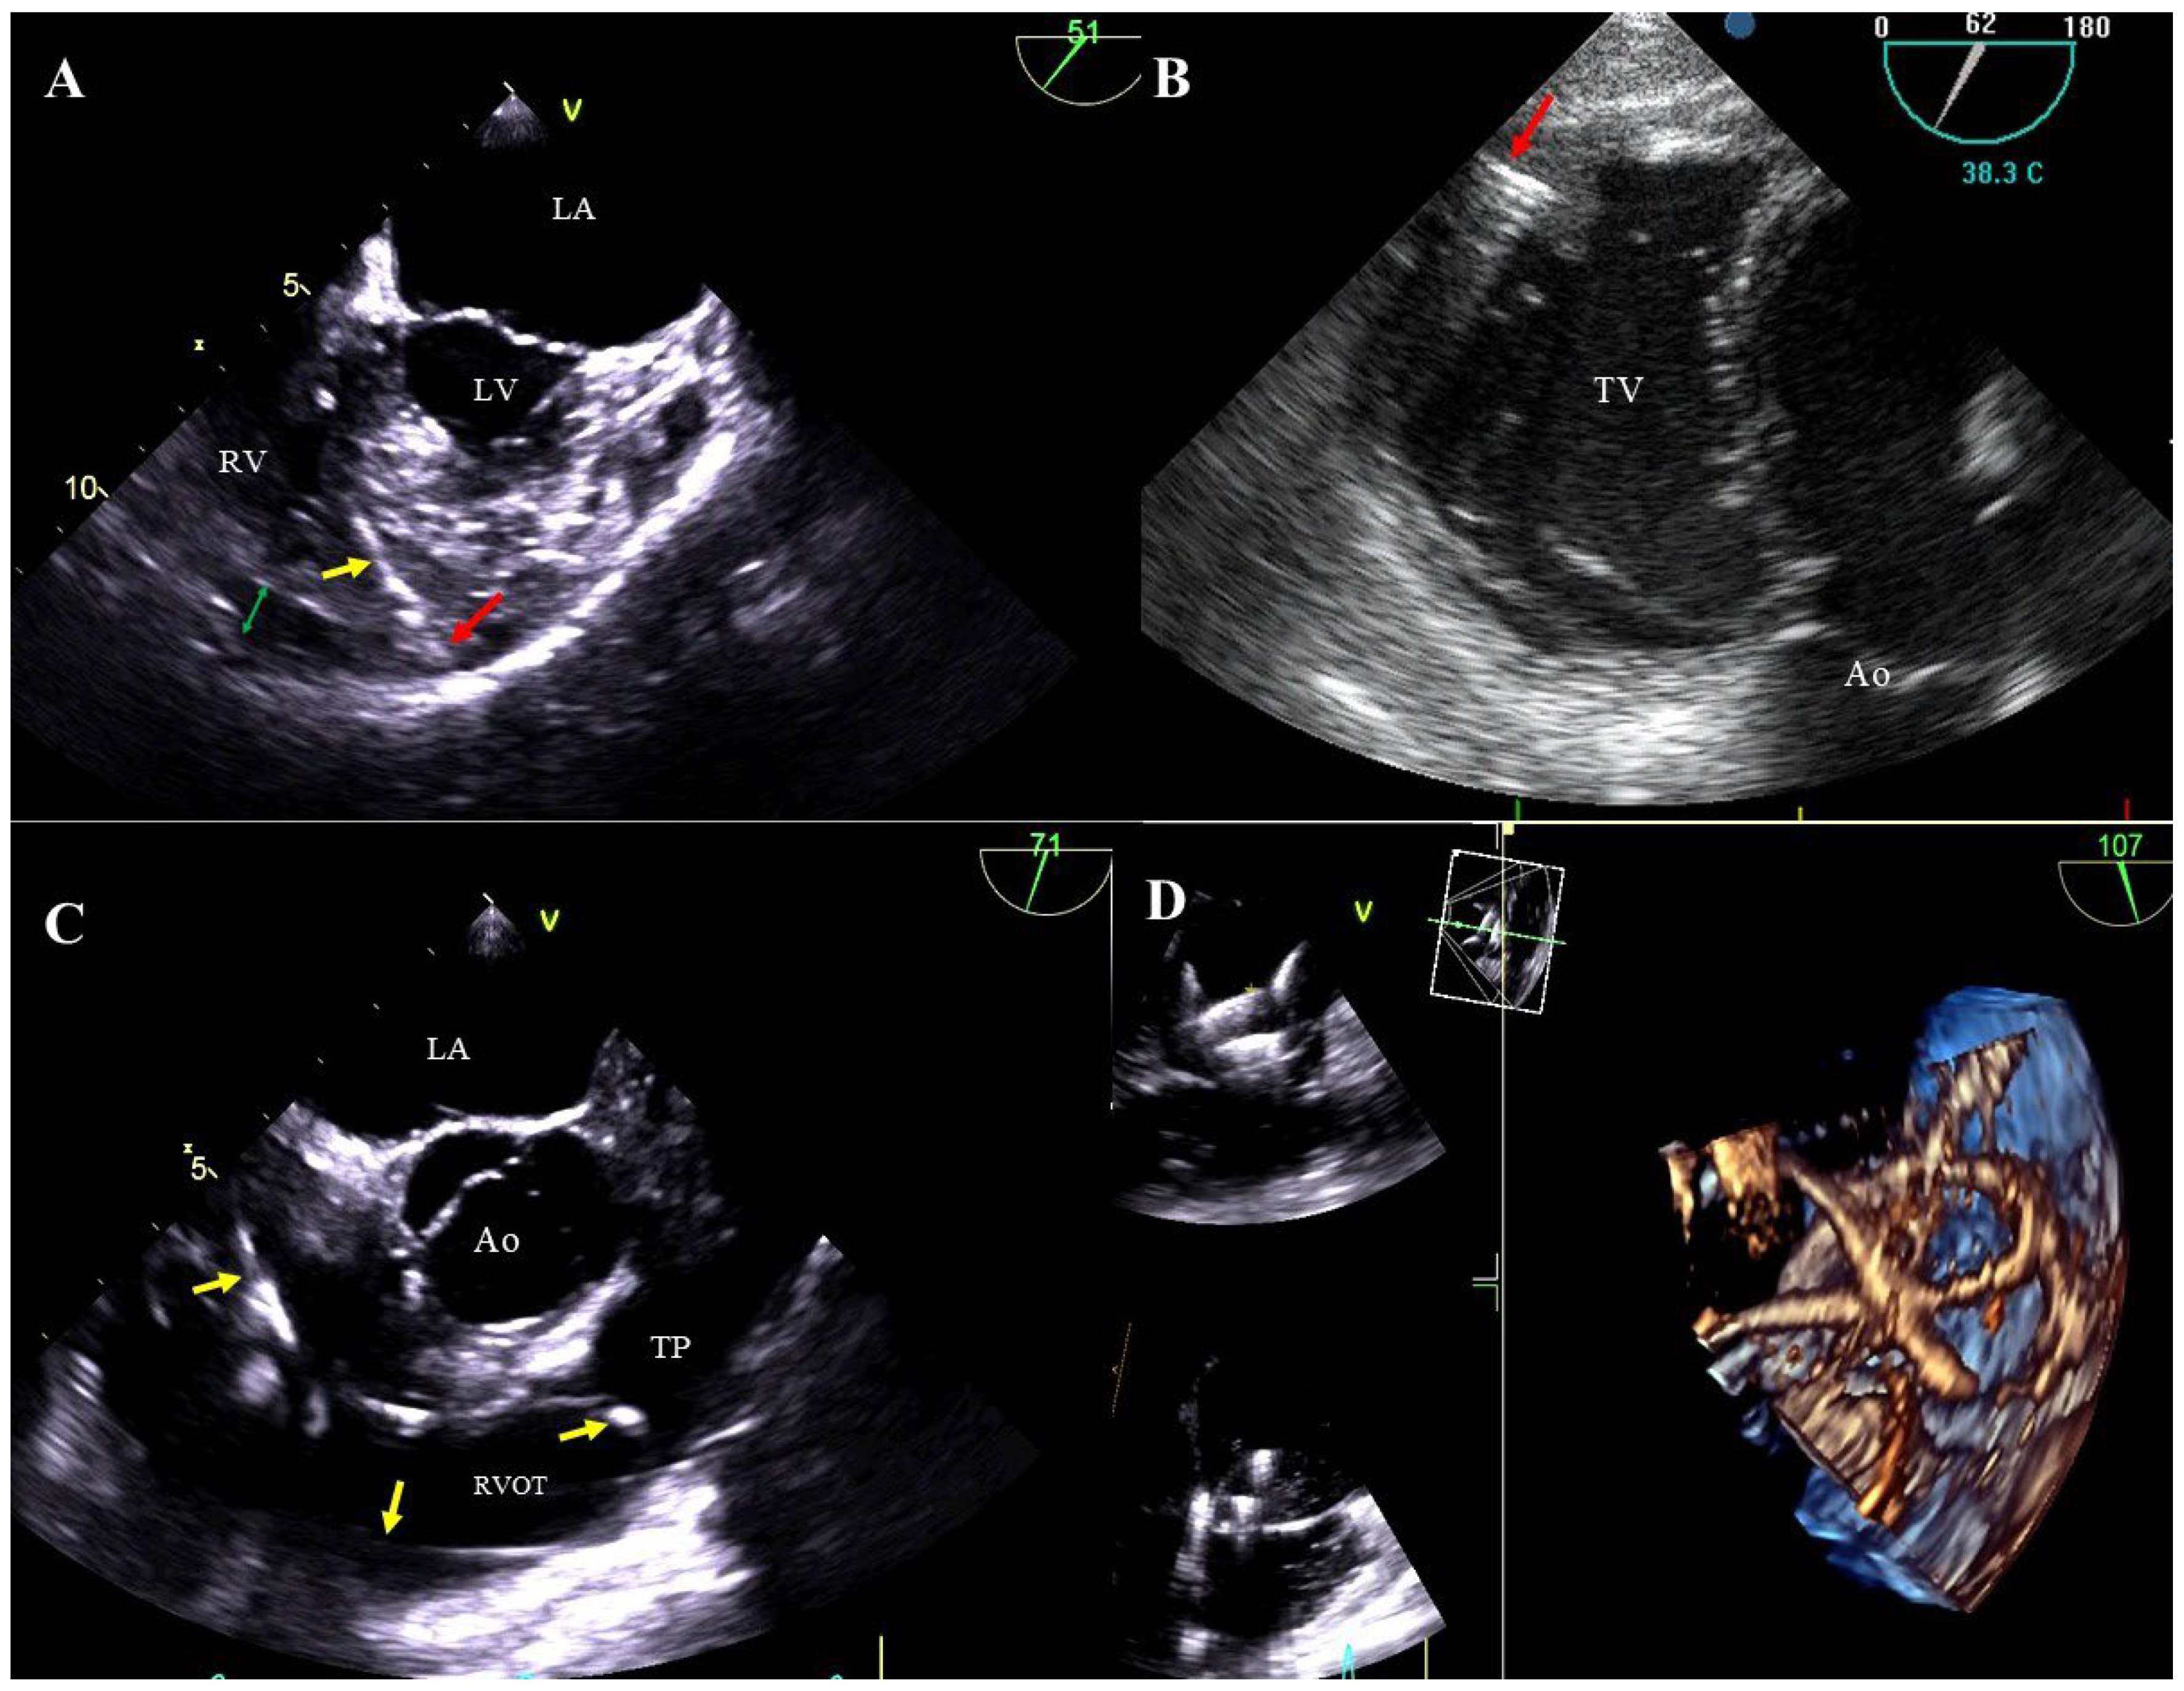

Figure 4. Tricuspid valve dysfunction caused by the presence of the electrode (TEE 2D, 3D). The lead (yellow arrow) in the tricuspid valve supports the septal leaflet and hinders proper coaptation of the leaflets (TEE 3D) (A,C). Severe tricuspid valve regurgitation resulting from the septal leaflet being pathologically supported by the lead (yellow arrow), (2D, color Doppler image from panel A) (B). The posterior leaflet of the tricuspid valve is perforated by the lead (yellow arrow) (D).

Lead-dependent tricuspid valve dysfunction (LDTVD): new valve regurgitation caused by the lead. The most common mechanism is impingement of the valve, adhesion of the lead to the leaflet or its perforation during implantation (Figure 4A–D, Movie S7).